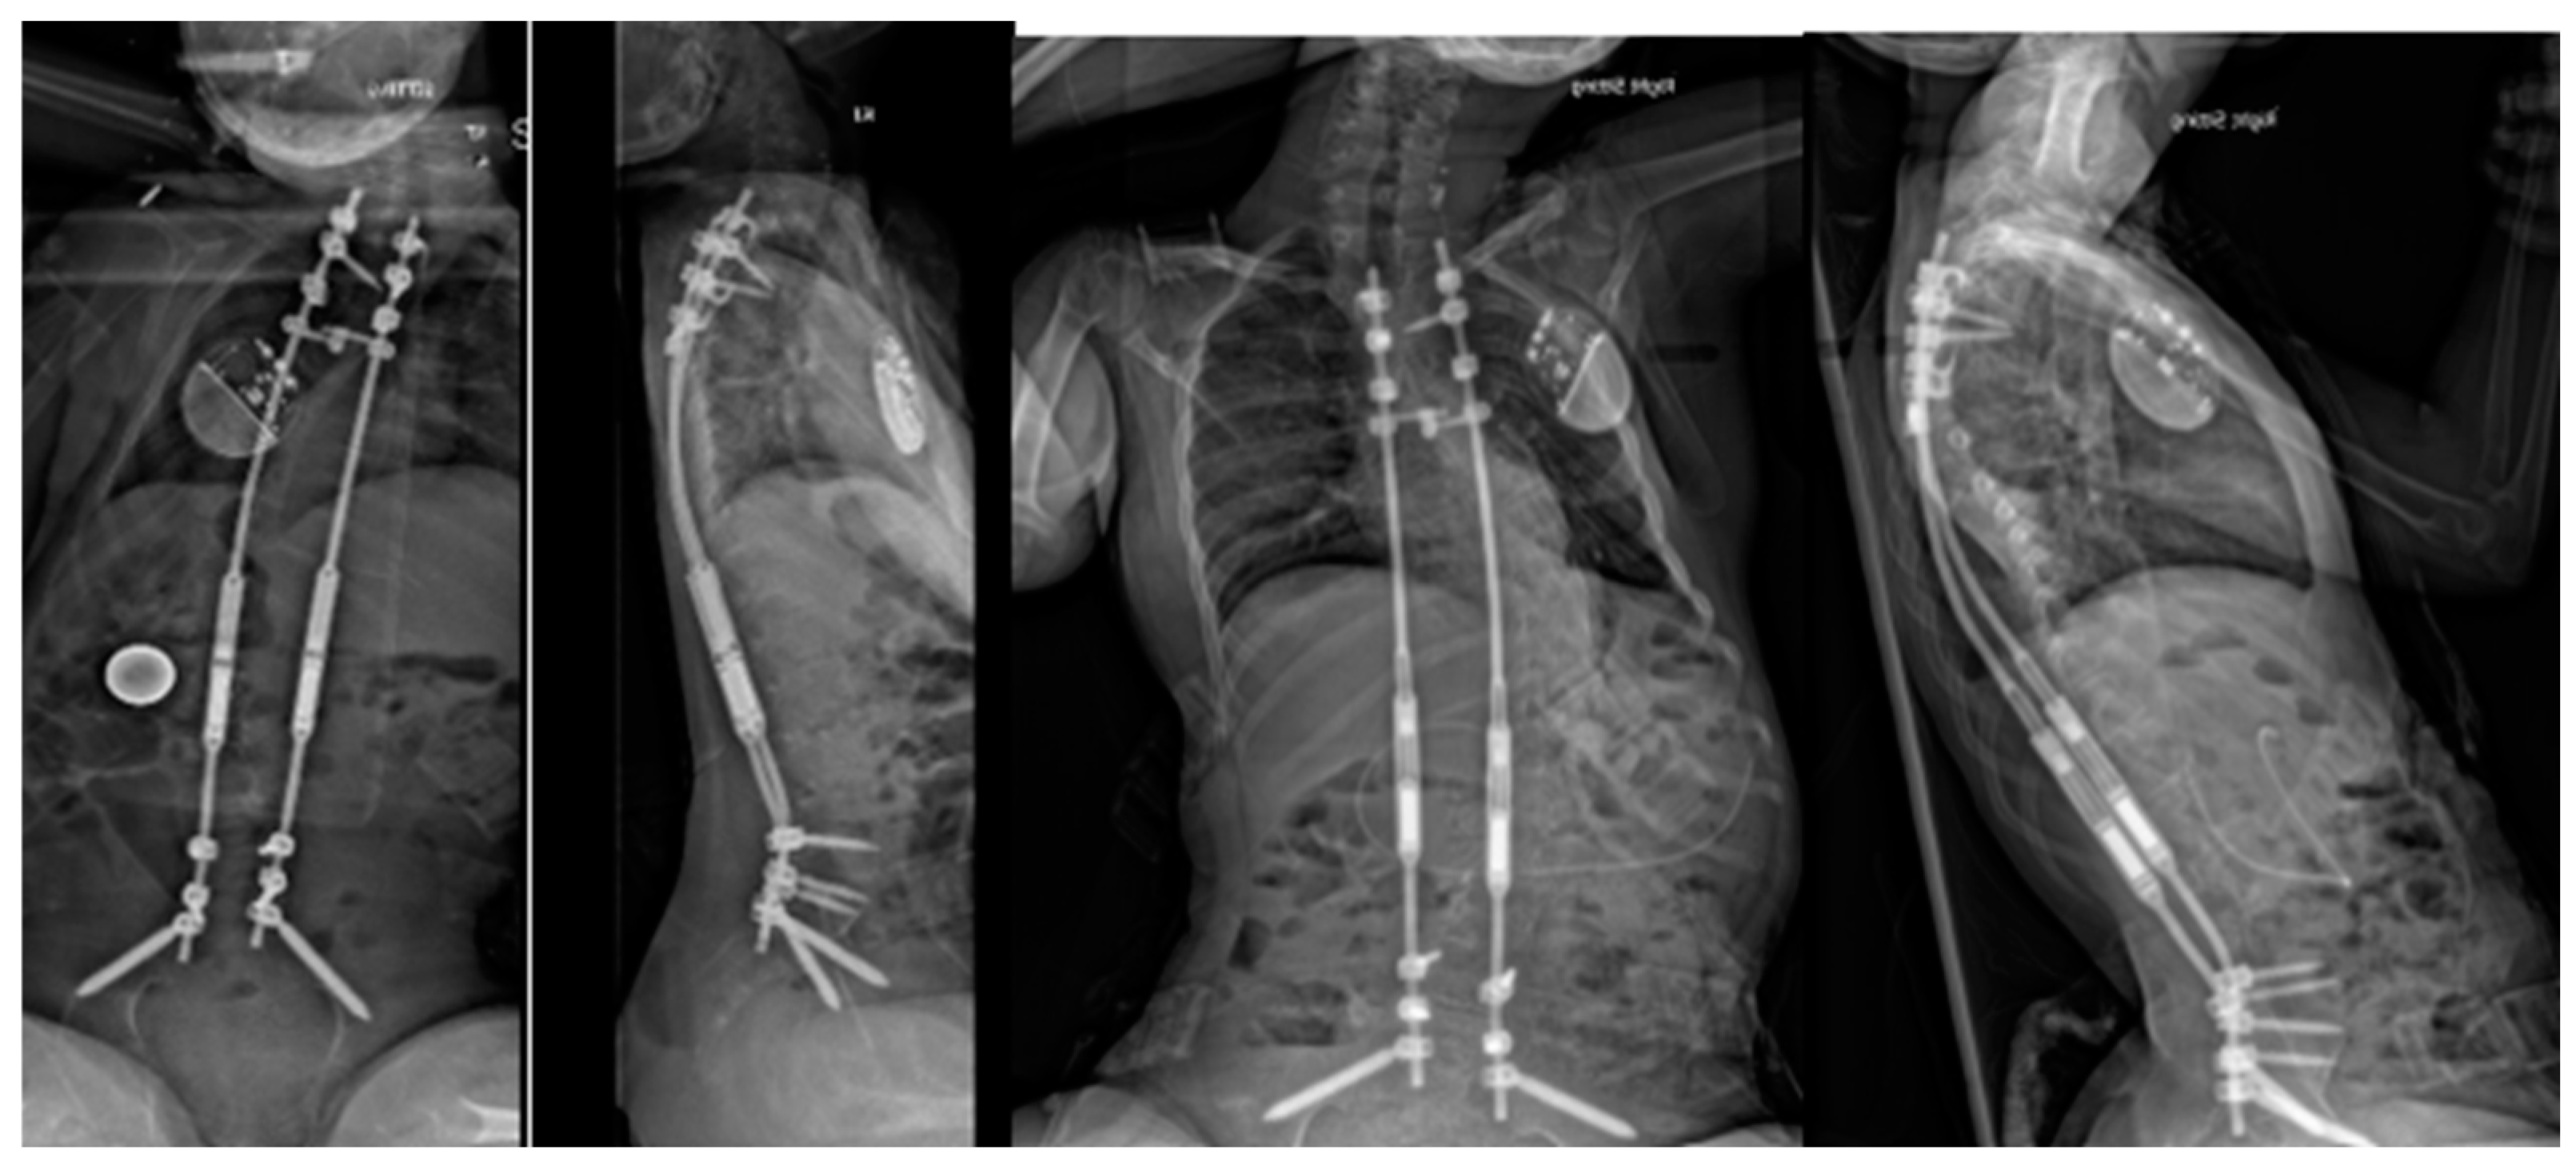

Originally described by Takaso in 1998, MCGRs were developed to address the complications that accompanied TGR lengthenings [38]. After initial implantation, patients are lengthened at short-term intervals in the clinic setting using an external remote control (ERC), eliminating the need for open lengthenings. MCGRs were shown to have similar treatment outcomes with respect to deformity correction and thoracic height, however, the device does have a notable complication profile of its own and requires careful patient selection for optimal use [39]. Various complications have been reported with MCGRs including implant or ERC malfunction and implant breakage or loosening with up to 33% revision rates [40,41]. Recently, concerns over metallosis have been brought forth with histologic changes of phagocytic cells seen in patients undergoing rod exchange with no long-term implications understood at this point [42]. Concerns remain over neurotoxic implications of increased serum titanium as it does cross the blood–brain barrier. Recent studies have suggested rates of unplanned return to the operating room within two years of implantation as high as 40% [43]. For these reasons, the device was suspended in certain countries. Only recently in February 2024 has the system been re-instated in the United Kingdom. Despite its imperfect execution, the implant is widely used. Careful patient selection is necessary when considering MCGRs. Per FDA and manufacturer guidelines, MCGRs are to be implanted only in skeletally immature patients less than 10 years of age with severe progressive spinal deformities associated with or at risk of thoracic insufficiency syndrome (TIS). A clinical example is shown pre-operatively in Figure 1 and post-operatively in Figure 2. MCGRs are inappropriate for patients with insufficient spinal height, inadequate skin and soft tissue cover, a stiff spinal curve, a sagittal curve apex above T3, hyperkyphosis, or patients requiring repetitive MRI [44]. Caution should be exercised in patients with increased soft tissue envelopes and BMI over 25, for example, those with Prader–Willi, which could preclude the transmission of magnetic impulses. Per manufacturer instructions for use, each MCGR unit should be implanted for no longer than 2 years. Further safety information and instructions for proper use are available on the manufacturer’s website and should be carefully studied by implanting surgeons.

Figure 2. Postoperative radiographs of the same patient at 6 weeks and 3 years postimplantation of magnetically controlled growing rods with sustained curve control and excellent sitting balance.